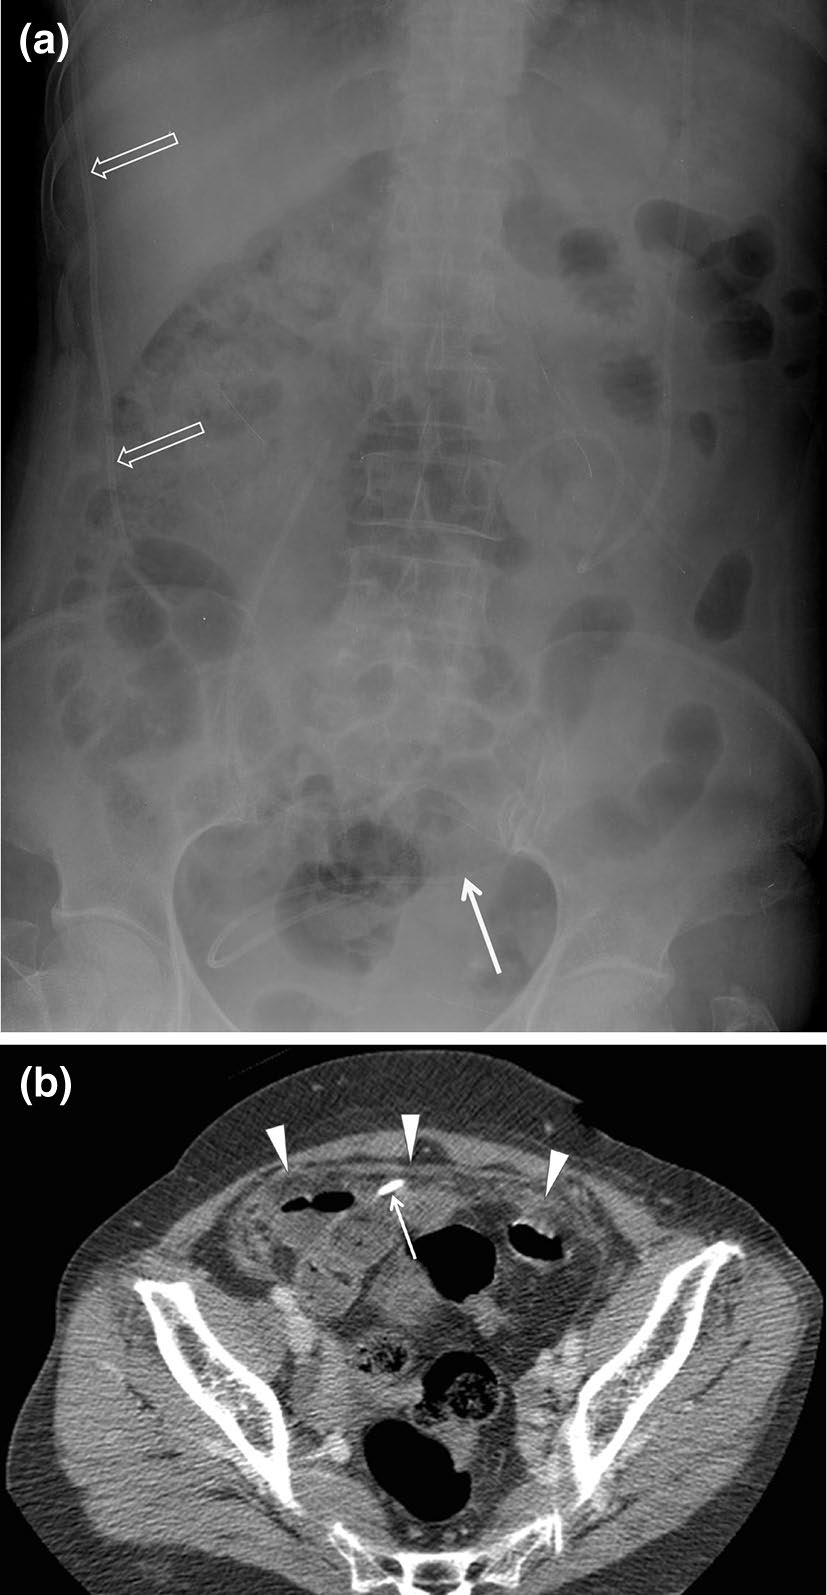

遗留手术纱布

遗留手术纱布是指在手术结束后意外遗留在患者体内的纱布或毛巾。据报道,手术纱布或棉签在腹部和盆腔中滞留的发生率约为0.02–1%[15]。残留手术纱布通常无症状,但有时可引起肉芽肿反应,并导致脓肿形成、肠梗阻或瘘管形成。大多数遗留的手术纱布可在平片X线检查中被发现,因为它们带有放射不透性标记。然而,没有明显放射不透性标记的手术纱布则只能通过计算机断层扫描识别。尽管残留手术纱布在计算机断层扫描上的表现多种多样,但漩涡状结构或含有气泡的海绵样模式是一种典型征象(图23)[15]。